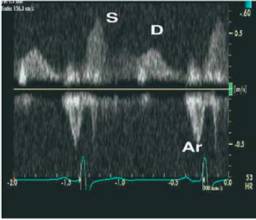

11、肺静脉血流频谱指标

●肺静脉血流频谱:S峰、D峰、S/D比值及Ar峰

●在LVEF小于40%时,与LA顺应性减低与LA平均压增高、增加有关